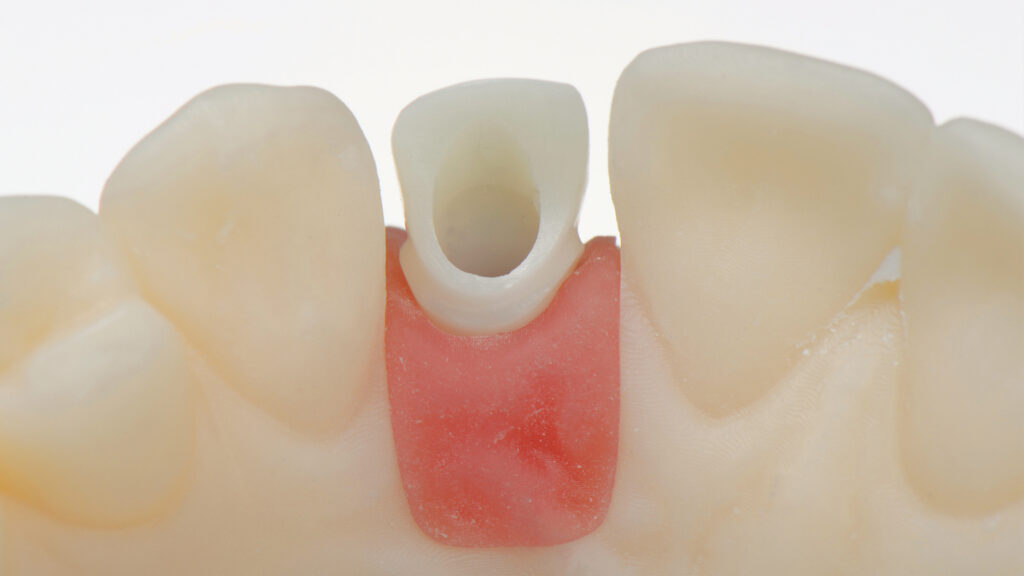

Herstellung des Eierschalen-Provisorium (TempShell)

Die STL-Datei der provisorischen Implantatkrone wird automatisch erzeugt, ein TempShell (Eierschalenprovisorium) konstruiert und die STL-Datei exportiert. TempShell ist ein verschraubtes Provisorium, das noch am Tag des chirurgischen Eingriffs eingesetzt werden kann. Es wird für jeden Patienten digital erstellt und kann mit DTX Studio Suite einfach an die Implantatposition angepasst werden. Anhand des Datensatzes wird CAD/CAM-gestützt das Provisorium aus PMMA gefräst (Abb. 11). Das gefräste Provisorium (TempShell) hat zwei Flügel. Diese sorgen für die richtige Position und Stabilität im Mund (Abb. 12 und 13). Durch On-Screen-Design-Verfahren passt das Provisorium perfekt auf das gedruckte Modell und in den vorgeschliffenen Gingivaverlauf (Abb. 14).